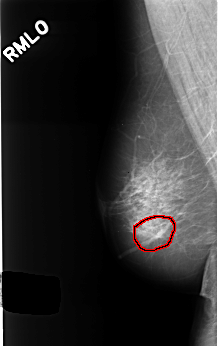

C_0398_1.RIGHT_MLO

RIGHT_MLO LINES 4488 PIXELS_PER_LINE 2832 BITS_PER_PIXEL 12 RESOLUTION 50 OVERLAY

FILE: C_0398_1.RIGHT_MLO.OVERLAY

TOTAL_ABNORMALITIES 1

ABNORMALITY 1

LESION_TYPE CALCIFICATION TYPE AMORPHOUS DISTRIBUTION CLUSTERED

ASSESSMENT 4

SUBTLETY 3

PATHOLOGY BENIGN

TOTAL_OUTLINES 1

BOUNDARY